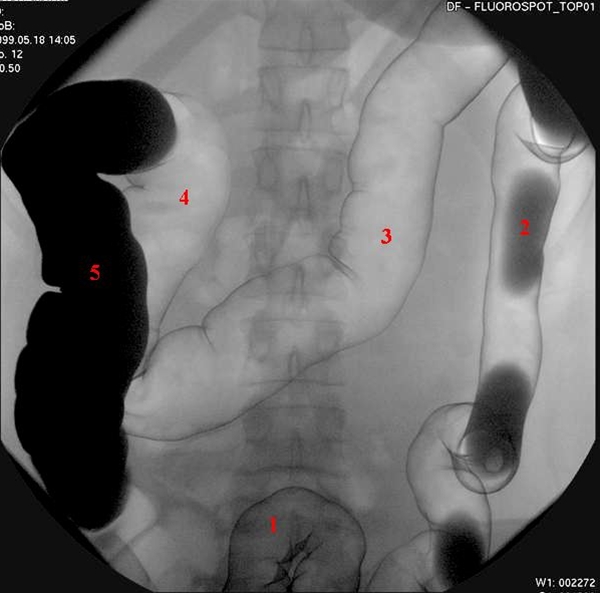

Colon dobbeltkontrast

Dobbeltkontrast-teknik med barium og luft til undersøgelse af tyktarm. Tallene henviser til forskellige segmenter af tyktarmen.

1. Sigmoideum

2. Descendens

3. Transversum

4. Højre flexur

5. Ascendens